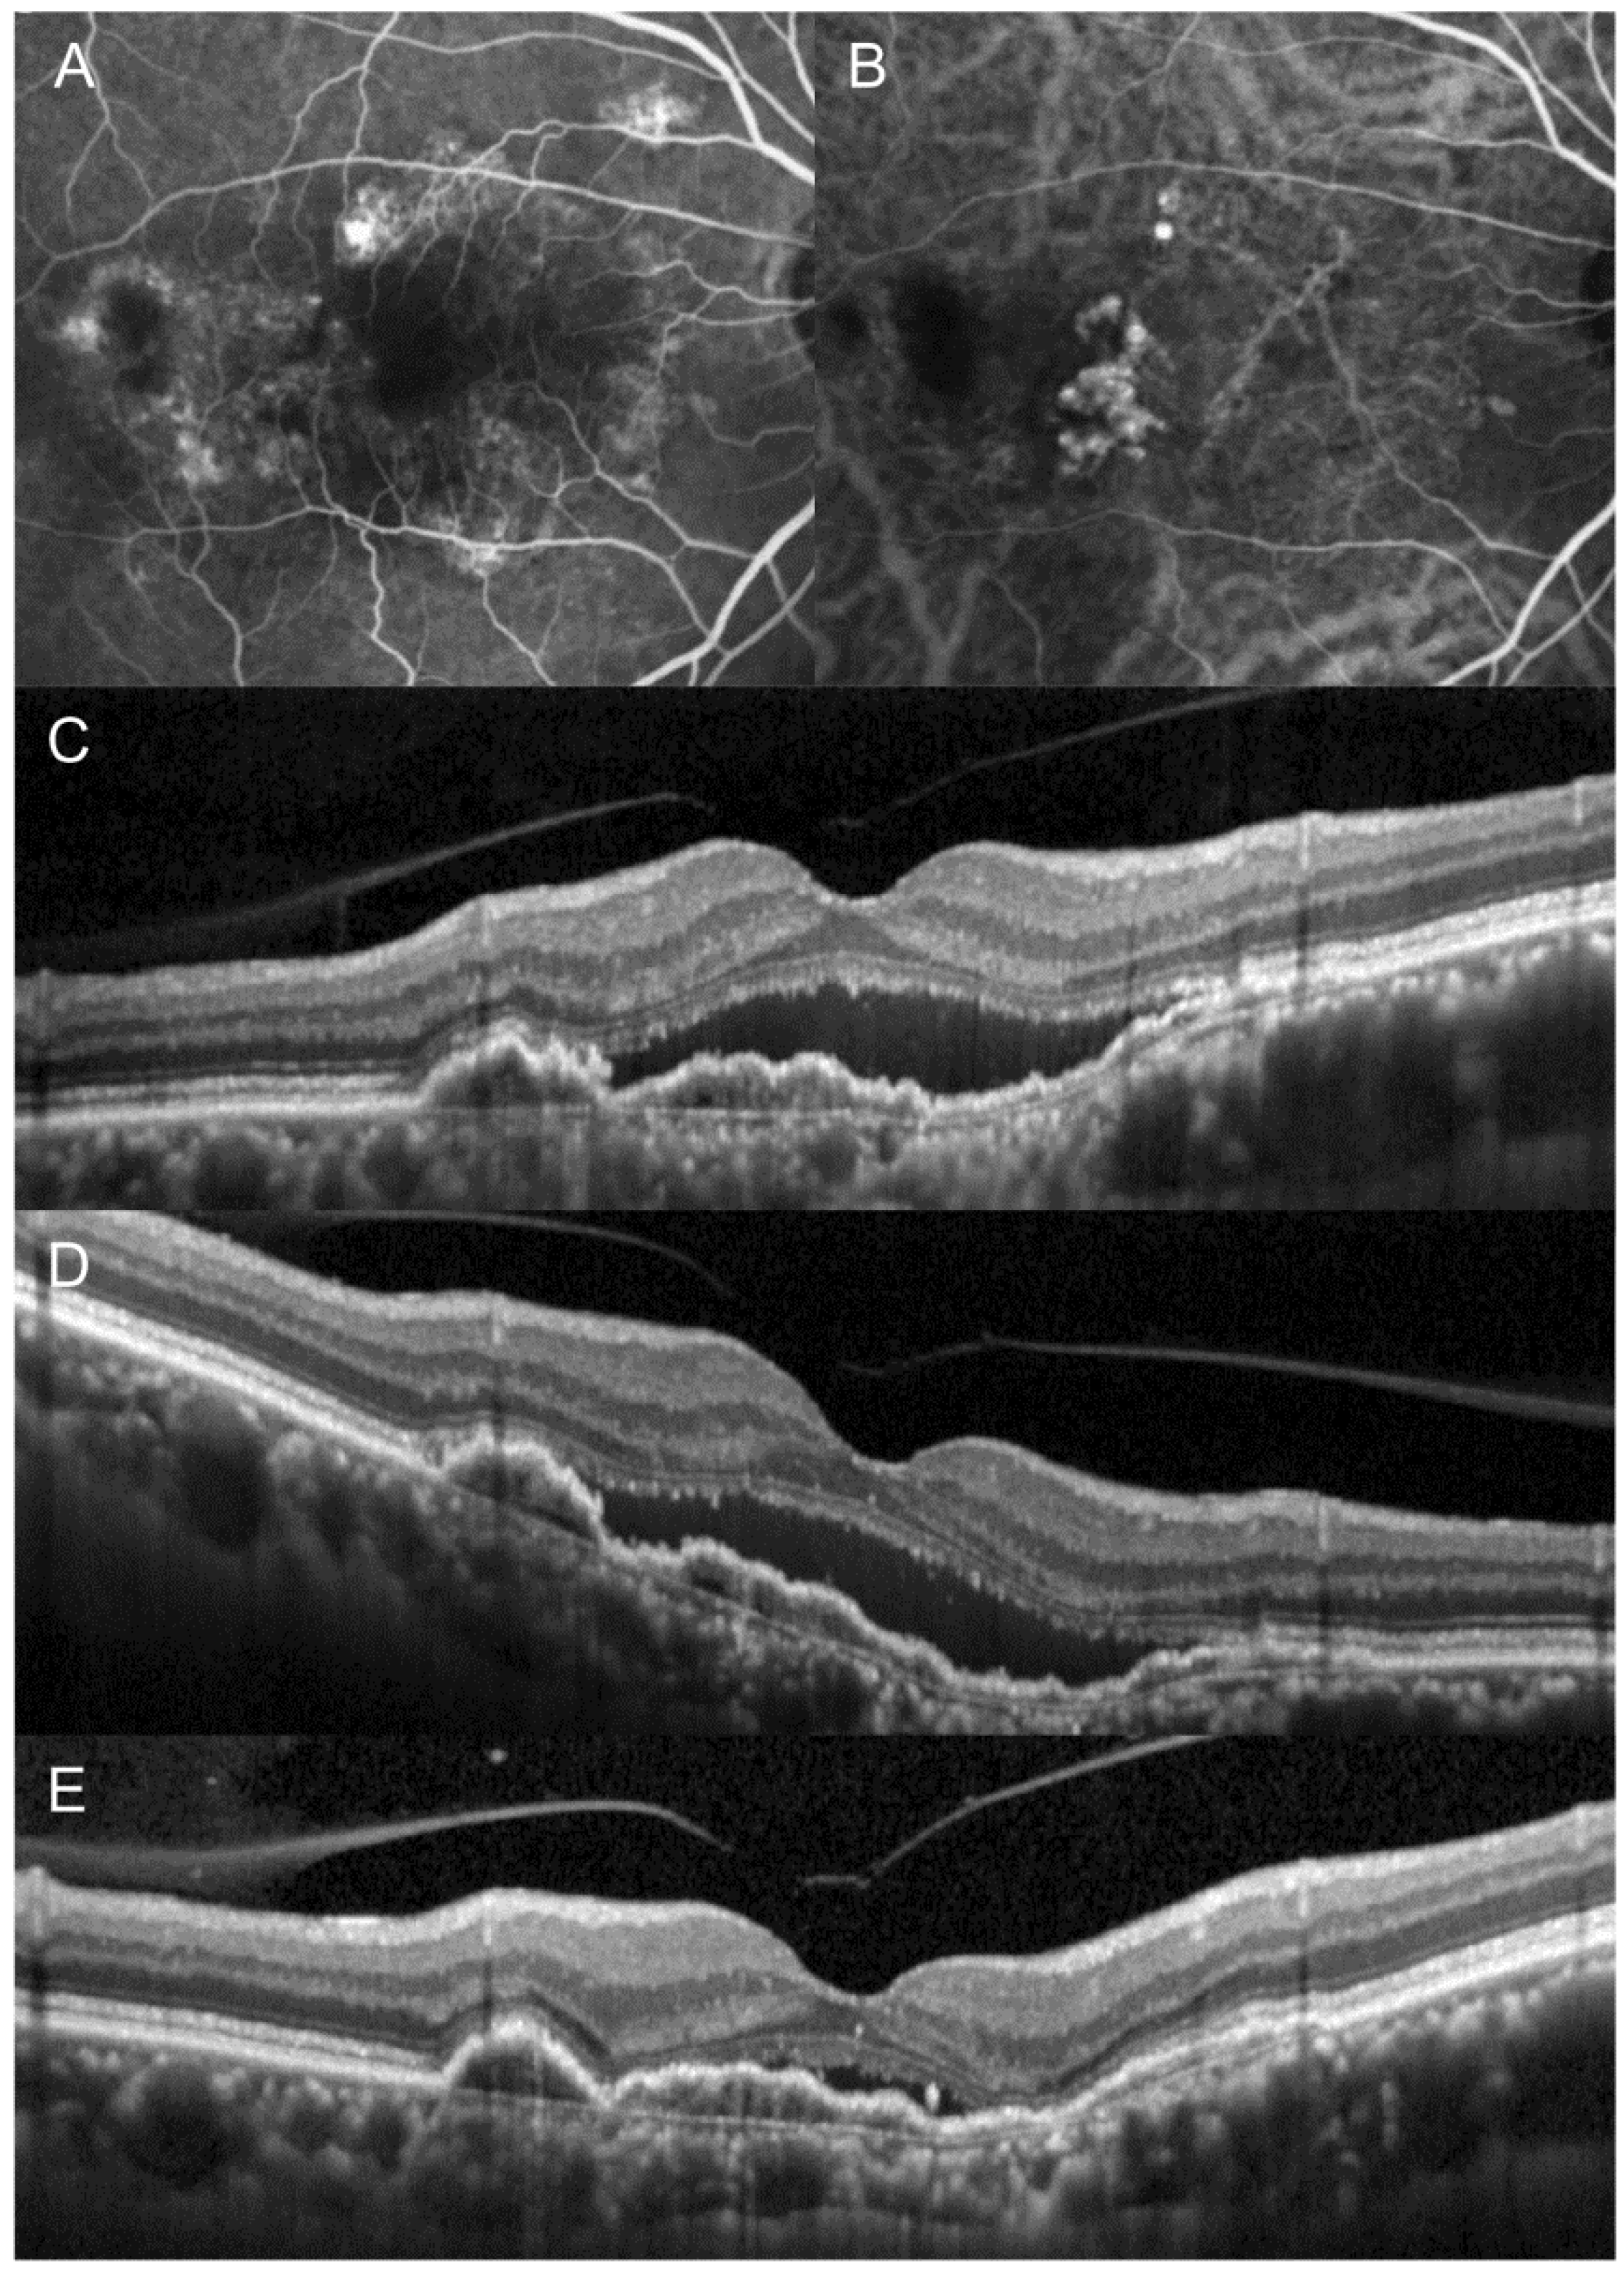

3. Results